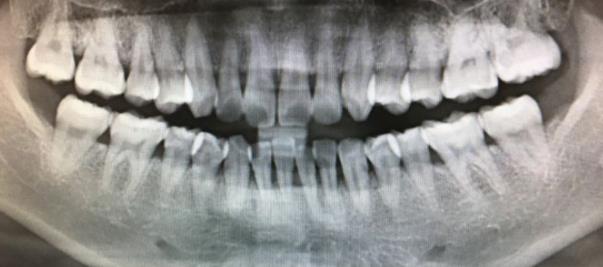

一般來說,到醫院做牙齒矯正之前需要做全麵的檢查,比如全景片,頭顱片等,醫生會(hui) 根據牙齒的詳細情況來製定合適的牙齒矯正方案,雖然有風險,但是也可以矯治了,不過需要提前預測風險值,出現問題了,需要及時停止矯治,然後及時進行處理。所以是否能不能做,需要先拍片後醫生專(zhuan) 業(ye) 綜合判斷,而且每個(ge) 人的牙根長短不一,牙根吸收的可能性不同,所以是否適合做矯治也不一定。